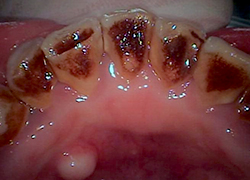

-

むし歯

お子様がむし歯になってしまったら早めに受診してください。年齢や状態によって治療法は変わりますが、当クリニックでは初めてのむし歯治療でも、お子様にできるだけ恐怖心を抱かせないように工夫をしながら診療しています。